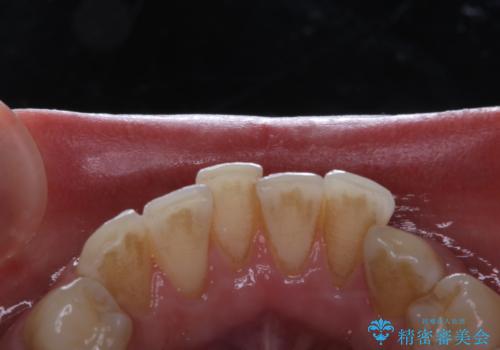

コーヒーの着色落としをPMTCでキレイに

- コーヒが好きで、ステインが付くことが気になるとのことで来院されました。PMTC30分コースを行いました。